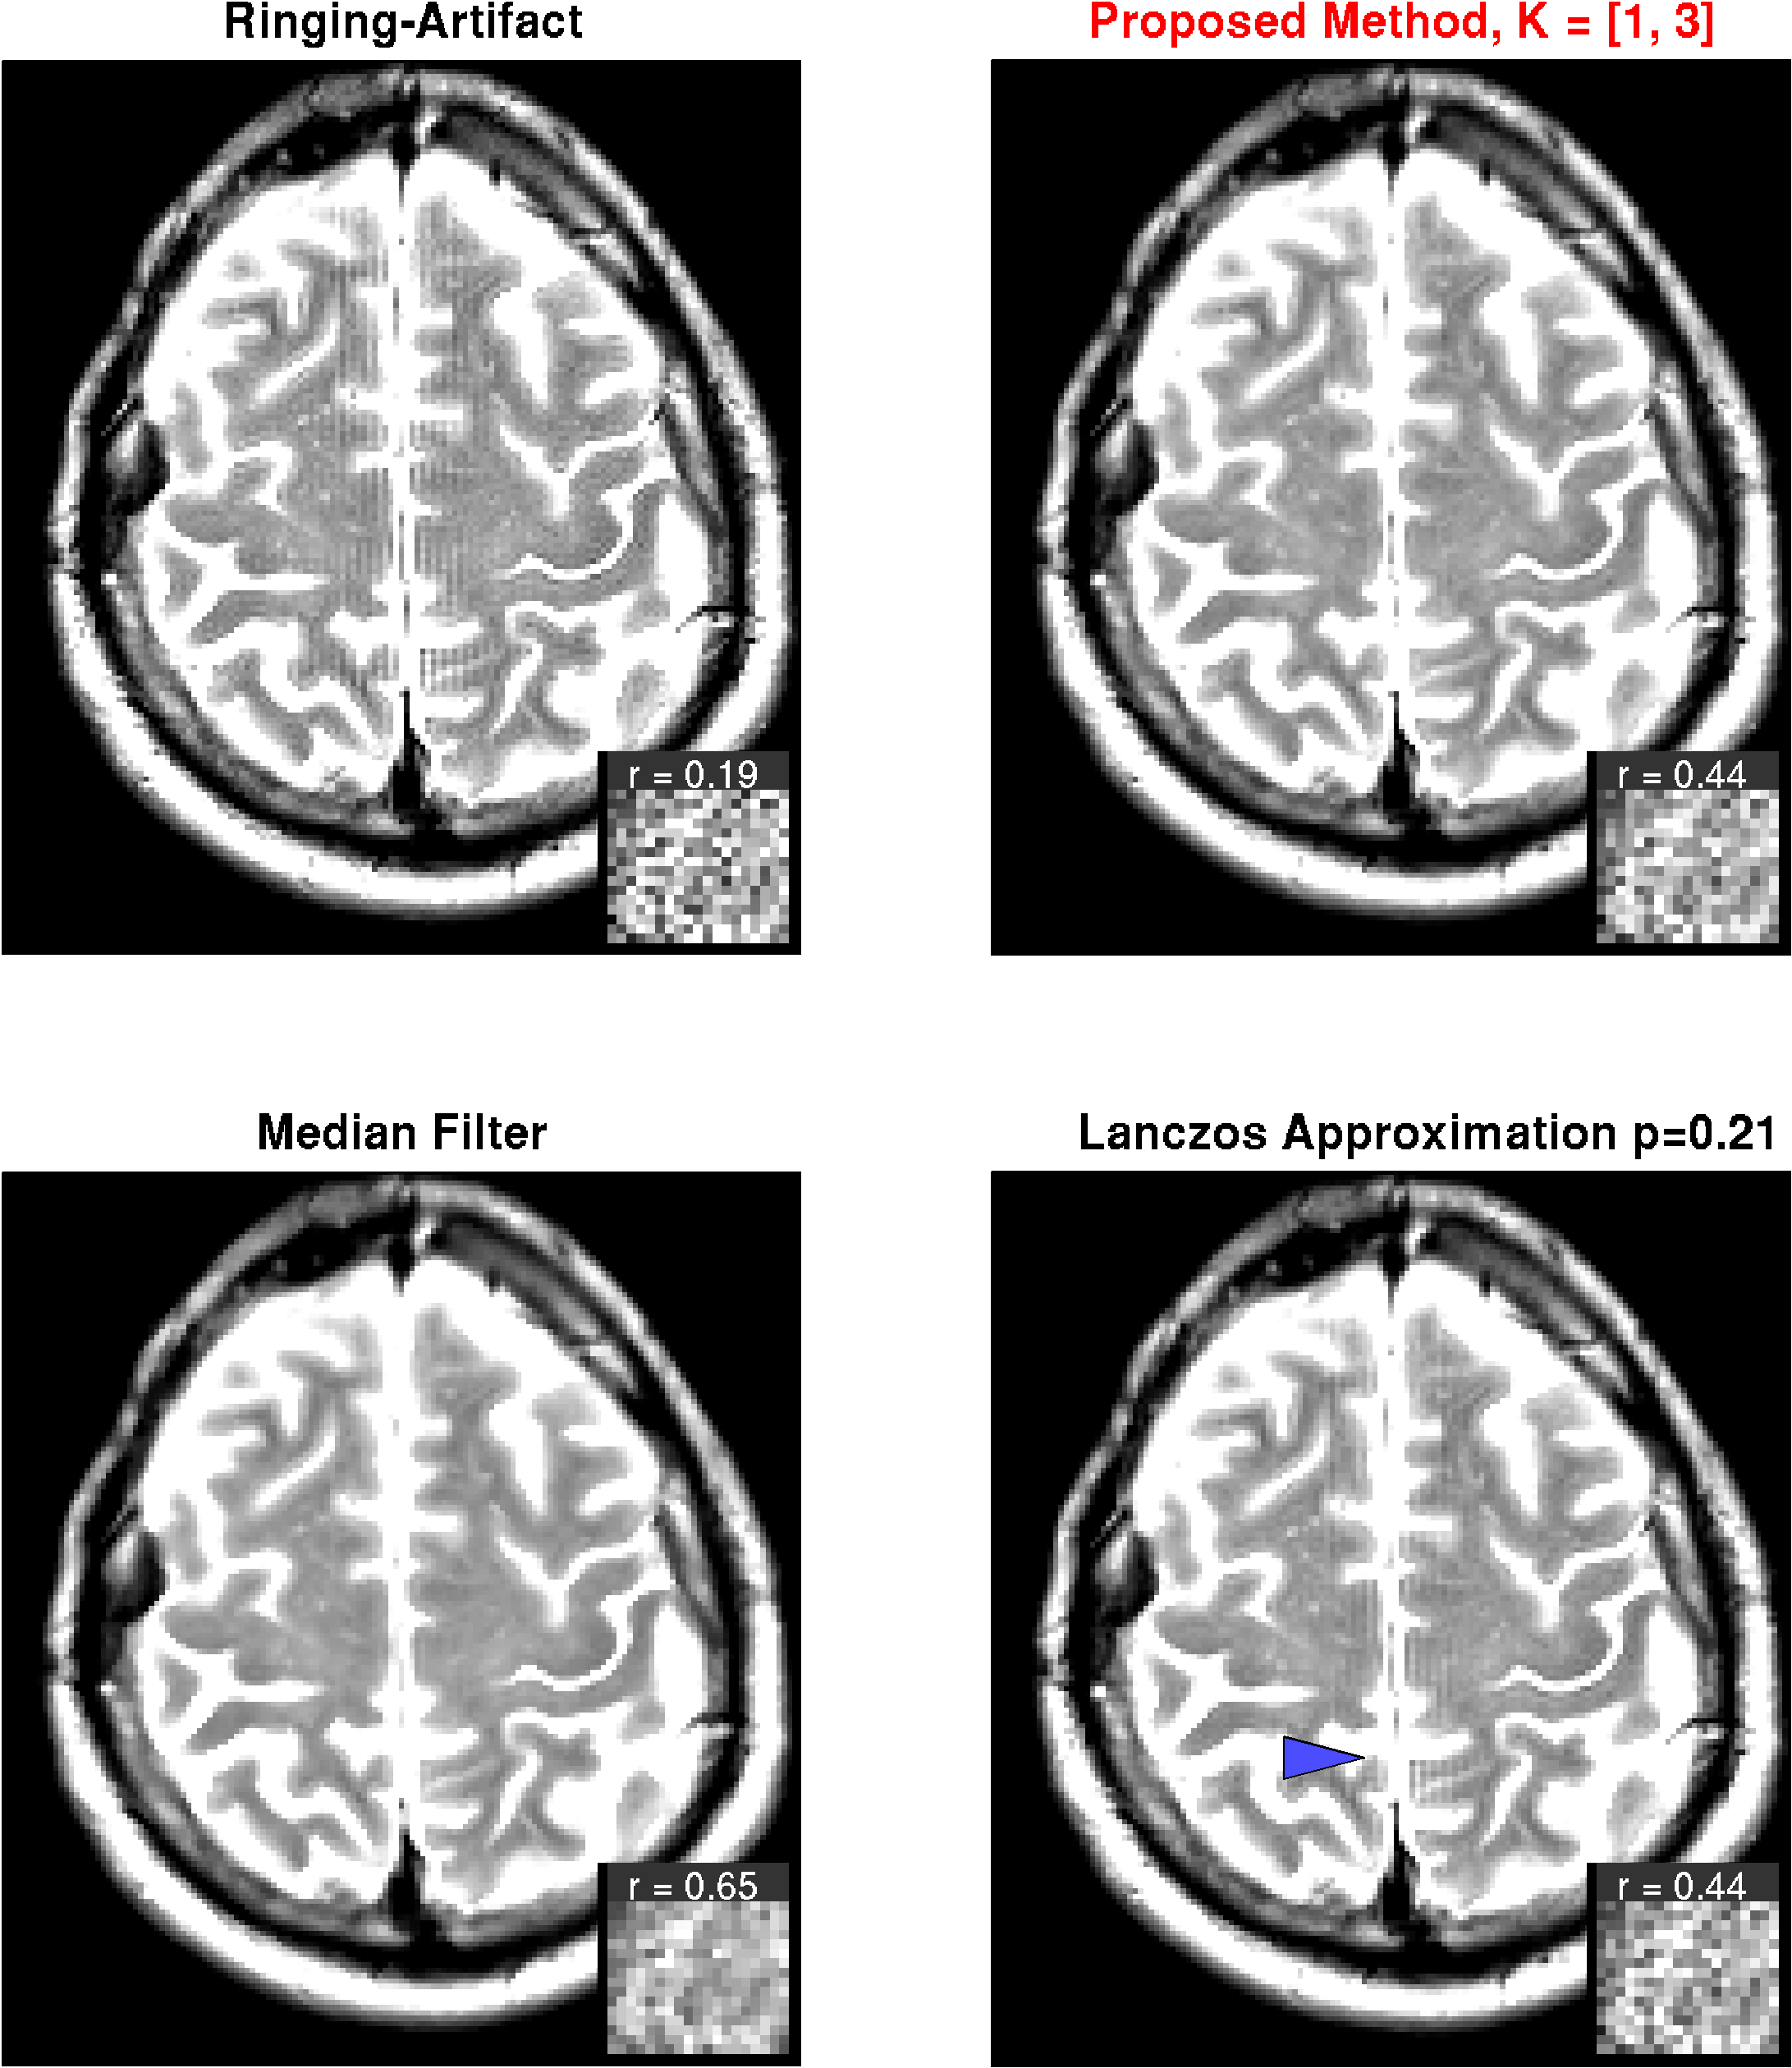

MRI Measurements

The method was applied to diffusion-weighted-images (DWI) with 70 directions, , using a gradient echo EPI sequence with , matrix size 104x104, resolution , performed on a 3T scanner (Siemens TIM TRIO, Siemens, Erlangen, Germany). No distortion correction was applied, as the involved correction methods already lead to significant filtering of the artifact, especially in phase direction. Due to the different image contrast for different -values, the artifact might even be amplified during post-processing of the diffusion parameters. Therefore, we also calculated diffusion maps, without and with artifact correction. We further applied the method to a -weighted image acquired with a turbo-spin-echo sequence, , resolution 1x1x5 on a 1.5T scanner (Siemens SONATA, Siemens, Erlangen, Germany). Both dataset were acquired in the context of clinical routine, written consent was obtained to use the data for scientific use.

MRI images

The results for DWI measurements are shown for one slice in Fig. 6. Apparently, the -images exhibit strong ringing artifacts, which is even more emphasized after diffusion calculation. The artifact can be reduced with both, the median filter and the Lanczos approximation with , however, at the cost of strong smoothing. With the proposed method on the other hand, the artifact can virtually completely be removed with minimal filtering. Results from the -weighted image given in Fig. 7. The findings are basically the same as for the DWI measurement.